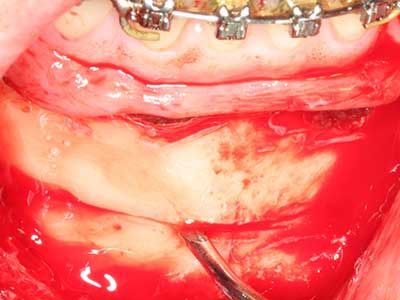

Quando le procedure chirurgiche vengono eseguite sull'osso nelle immediate vicinanze di strutture sensibili, come vasi sanguigni o nervi, gli strumenti rotanti pongono un rischio significativo di lesione iatrogena. I dispositivi piezoelettrici possono essere utili per la preparazione delle coperture ossee e la rimozione del tessuto duro in prossimità dei nervi, in particolare per la loro esposizione dopo una lesione iatrogena, ma anche durante la lateralizzazione dei nervi per le procedure di resezione e ricostruzione o il posizionamento di impianti (figg. 17-20). Il contatto leggero tra puntina piezoelettrica e nervo non causa generalmente danni, ma se si procede senza prestare attenzione con movimenti a sega o raccordi con residui di substrati ossei possono verificarsi danni al nervo temporanei o anche permanenti. Il rischio di danno, tuttavia, è considerato sostanzialmente inferiore al rischio presente utilizzando seghe o frese (Pereira, Gealh et al. 2014).

Come dimostrato in passato, pressoché qualsiasi procedura chirurgica che interessa il tessuto osseo rappresenta una possibile indicazione per la piezochirurgia. Quindi, per la preparazione del segmento mobile nella distrazione osteogenetica (figg. 23-25) e nell'osteotomia con tecnica a sandwich si utilizzano appositi raccordi per non danneggiare l'apporto sanguigno alla sezione della cresta, elemento essenziale per la corretta esecuzione di entrambe le tecniche (Gonzalez-Garcia, Diniz-Freitas et al. 2008).